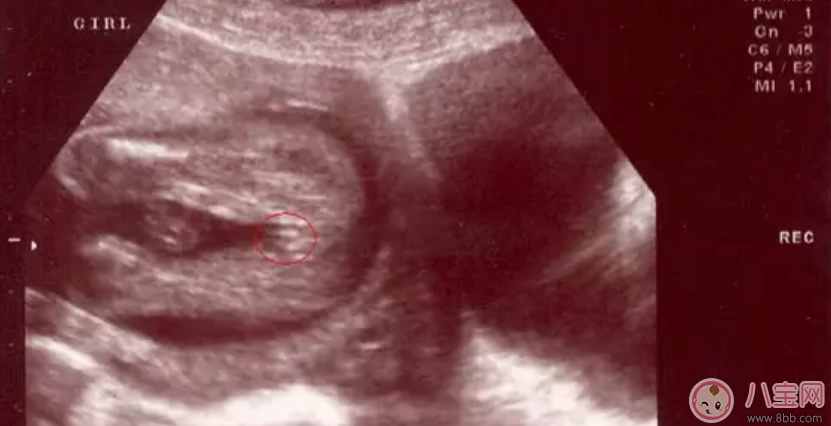

女寶寶四維彩超圖

三條白線是明顯的女寶特征,如果沒(méi)有看到明顯的三條白線,就看兩腿之間有沒(méi)有突出的東東,且中間有小凹槽的,就是女寶